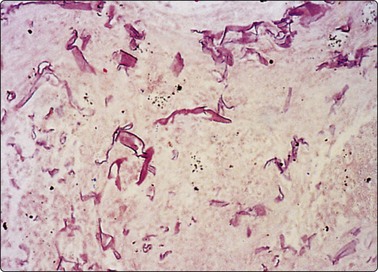

Negative images of mycobacteria may be seen in the background serum and cytoplasm of histiocytes in the Giemsa stain (Fig. 18.5), and the beaded 3–4-micron bacilli stain in the ZN (Fig. 18.6A) and auramine (Fig. 18.6B) stains and autoflouresce in the Papstain.41

image

Fig. 18.5 Negative image of curved beaded atypical mycobacteria in histiocyte cytoplasm and serum background; note tendency for several bacilli to attach end to end (HIV-positive patient) (Giemsa, ×1000).

(Courtesy Dr William Geddie, Toronto, Canada)

image image

Fig. 18.6 (A) Curved beaded mycobacteria in Ziehl Neelsen stain (ZN, ×1000); (B) Mycobacteria in Auramine stain (Auramine, ×1000).